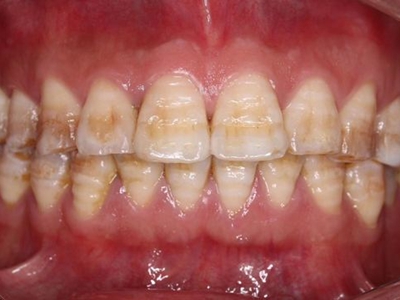

牙釉质发育不全牙齿有条纹凹陷图

牙釉质发育不全患者牙齿上出现棕褐色的条纹凹陷,部分融合成一小片,牙齿整体发白,形态较完整,患者无明显疼痛、流血等异常表现。